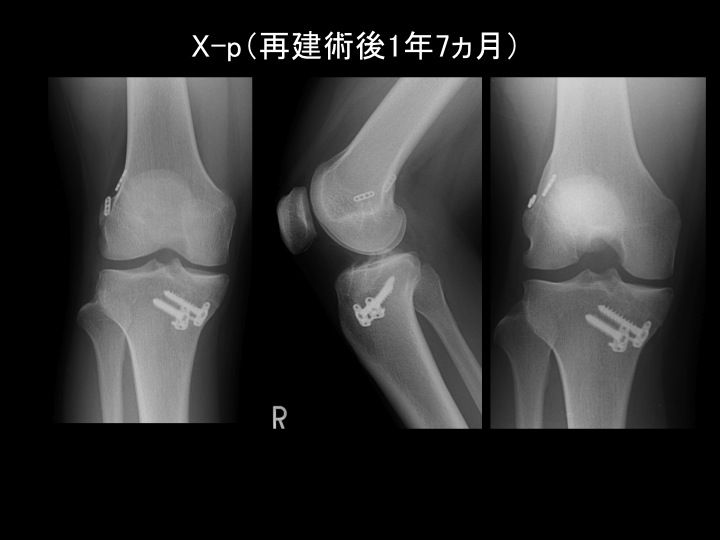

半月板のすべて−解剖から縫合手術,再生治療まで | 宗田 大。メジカルビュー社|整形外科|半月板のすべて。膝外側半月板後節の弁状断裂(無血管野) に対する縫合術。「半月板のすべて 解剖から手術、再生医療まで」宗田 大 / 関矢 一郎 / 古賀 英之メジカルビュー社定価: ¥ 13200裁断済みのためやや傷や汚れありとしていますが、状態は大変良好であり、書き込みやマーカー等もありません。スポーツ整形外科・関節鏡手術 | 整形外科 | 【公式】 大阪市立。#宗田大 #宗田_大 #関矢一郎 #関矢_一郎 #古賀英之 #古賀_英之 #本 #自然/医療・薬学・健康

• 膝外側半月板後節の弁状断裂(無血管野) に対する縫合術